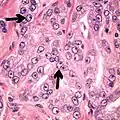

- Less specific findings.

- Mitoses (also seen in for example high-grade prostatic intraepithelial neoplasia (HGPIN) and prostate inflammation).[4]

Adenocarcinoma with two mitoses in reactive epithelium.